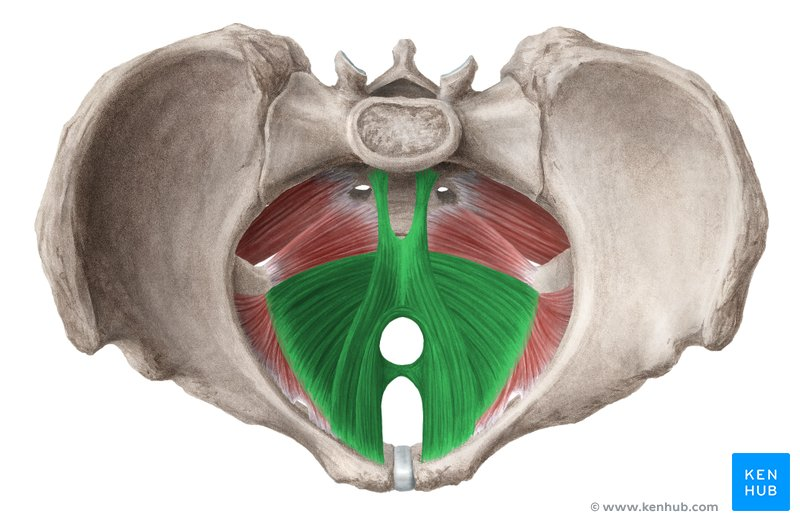

m levator ani

coccygeus